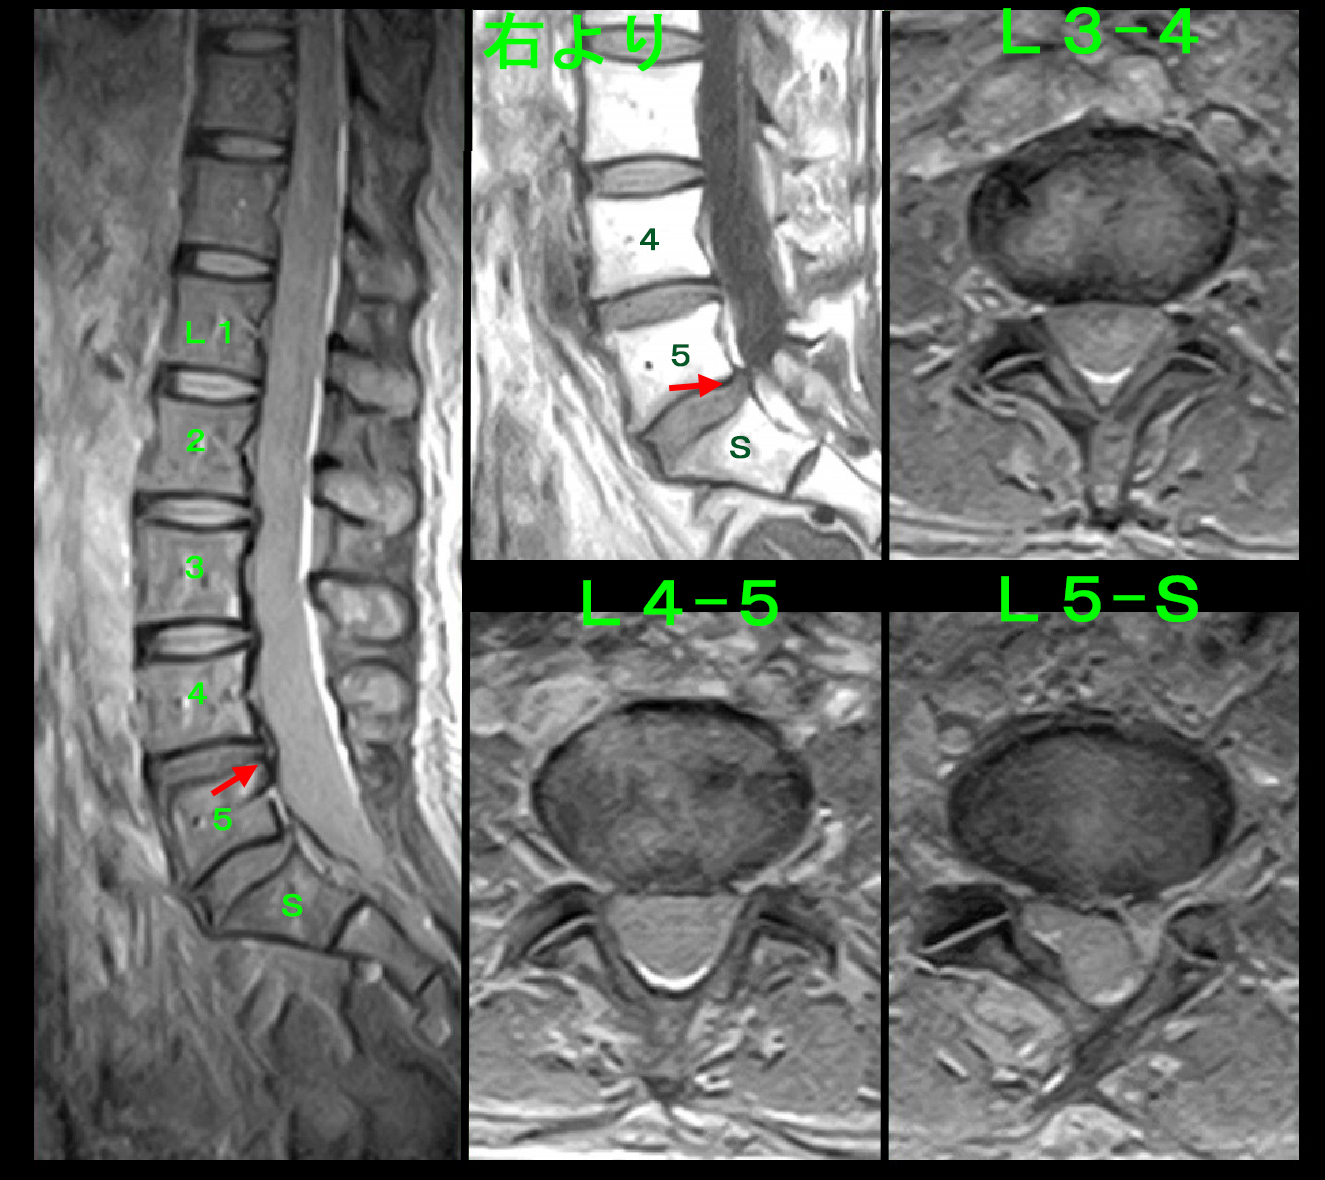

50才女 MR1.jpg

しかし、VAS8の痛みの原因となりそうな所見は確認されず、L4-5とL5-Sに軽微な椎間板ヘルニアを認める程度の所見です。服薬でVAS8→1~2(2はわずかに痛い)に軽減したそうですが、腹部と両下肢に浮腫を生じたため5日で服薬を中止したそうです。ロキソニンで浮腫の副作用が出ることがあります。服薬を中止すると腰痛はVAS4~5(4は多少痛い)に戻ったそうです。この経過で頚部痛はVAS7(6はけっこう痛い、8がとても痛い)のままであったとのことでした。